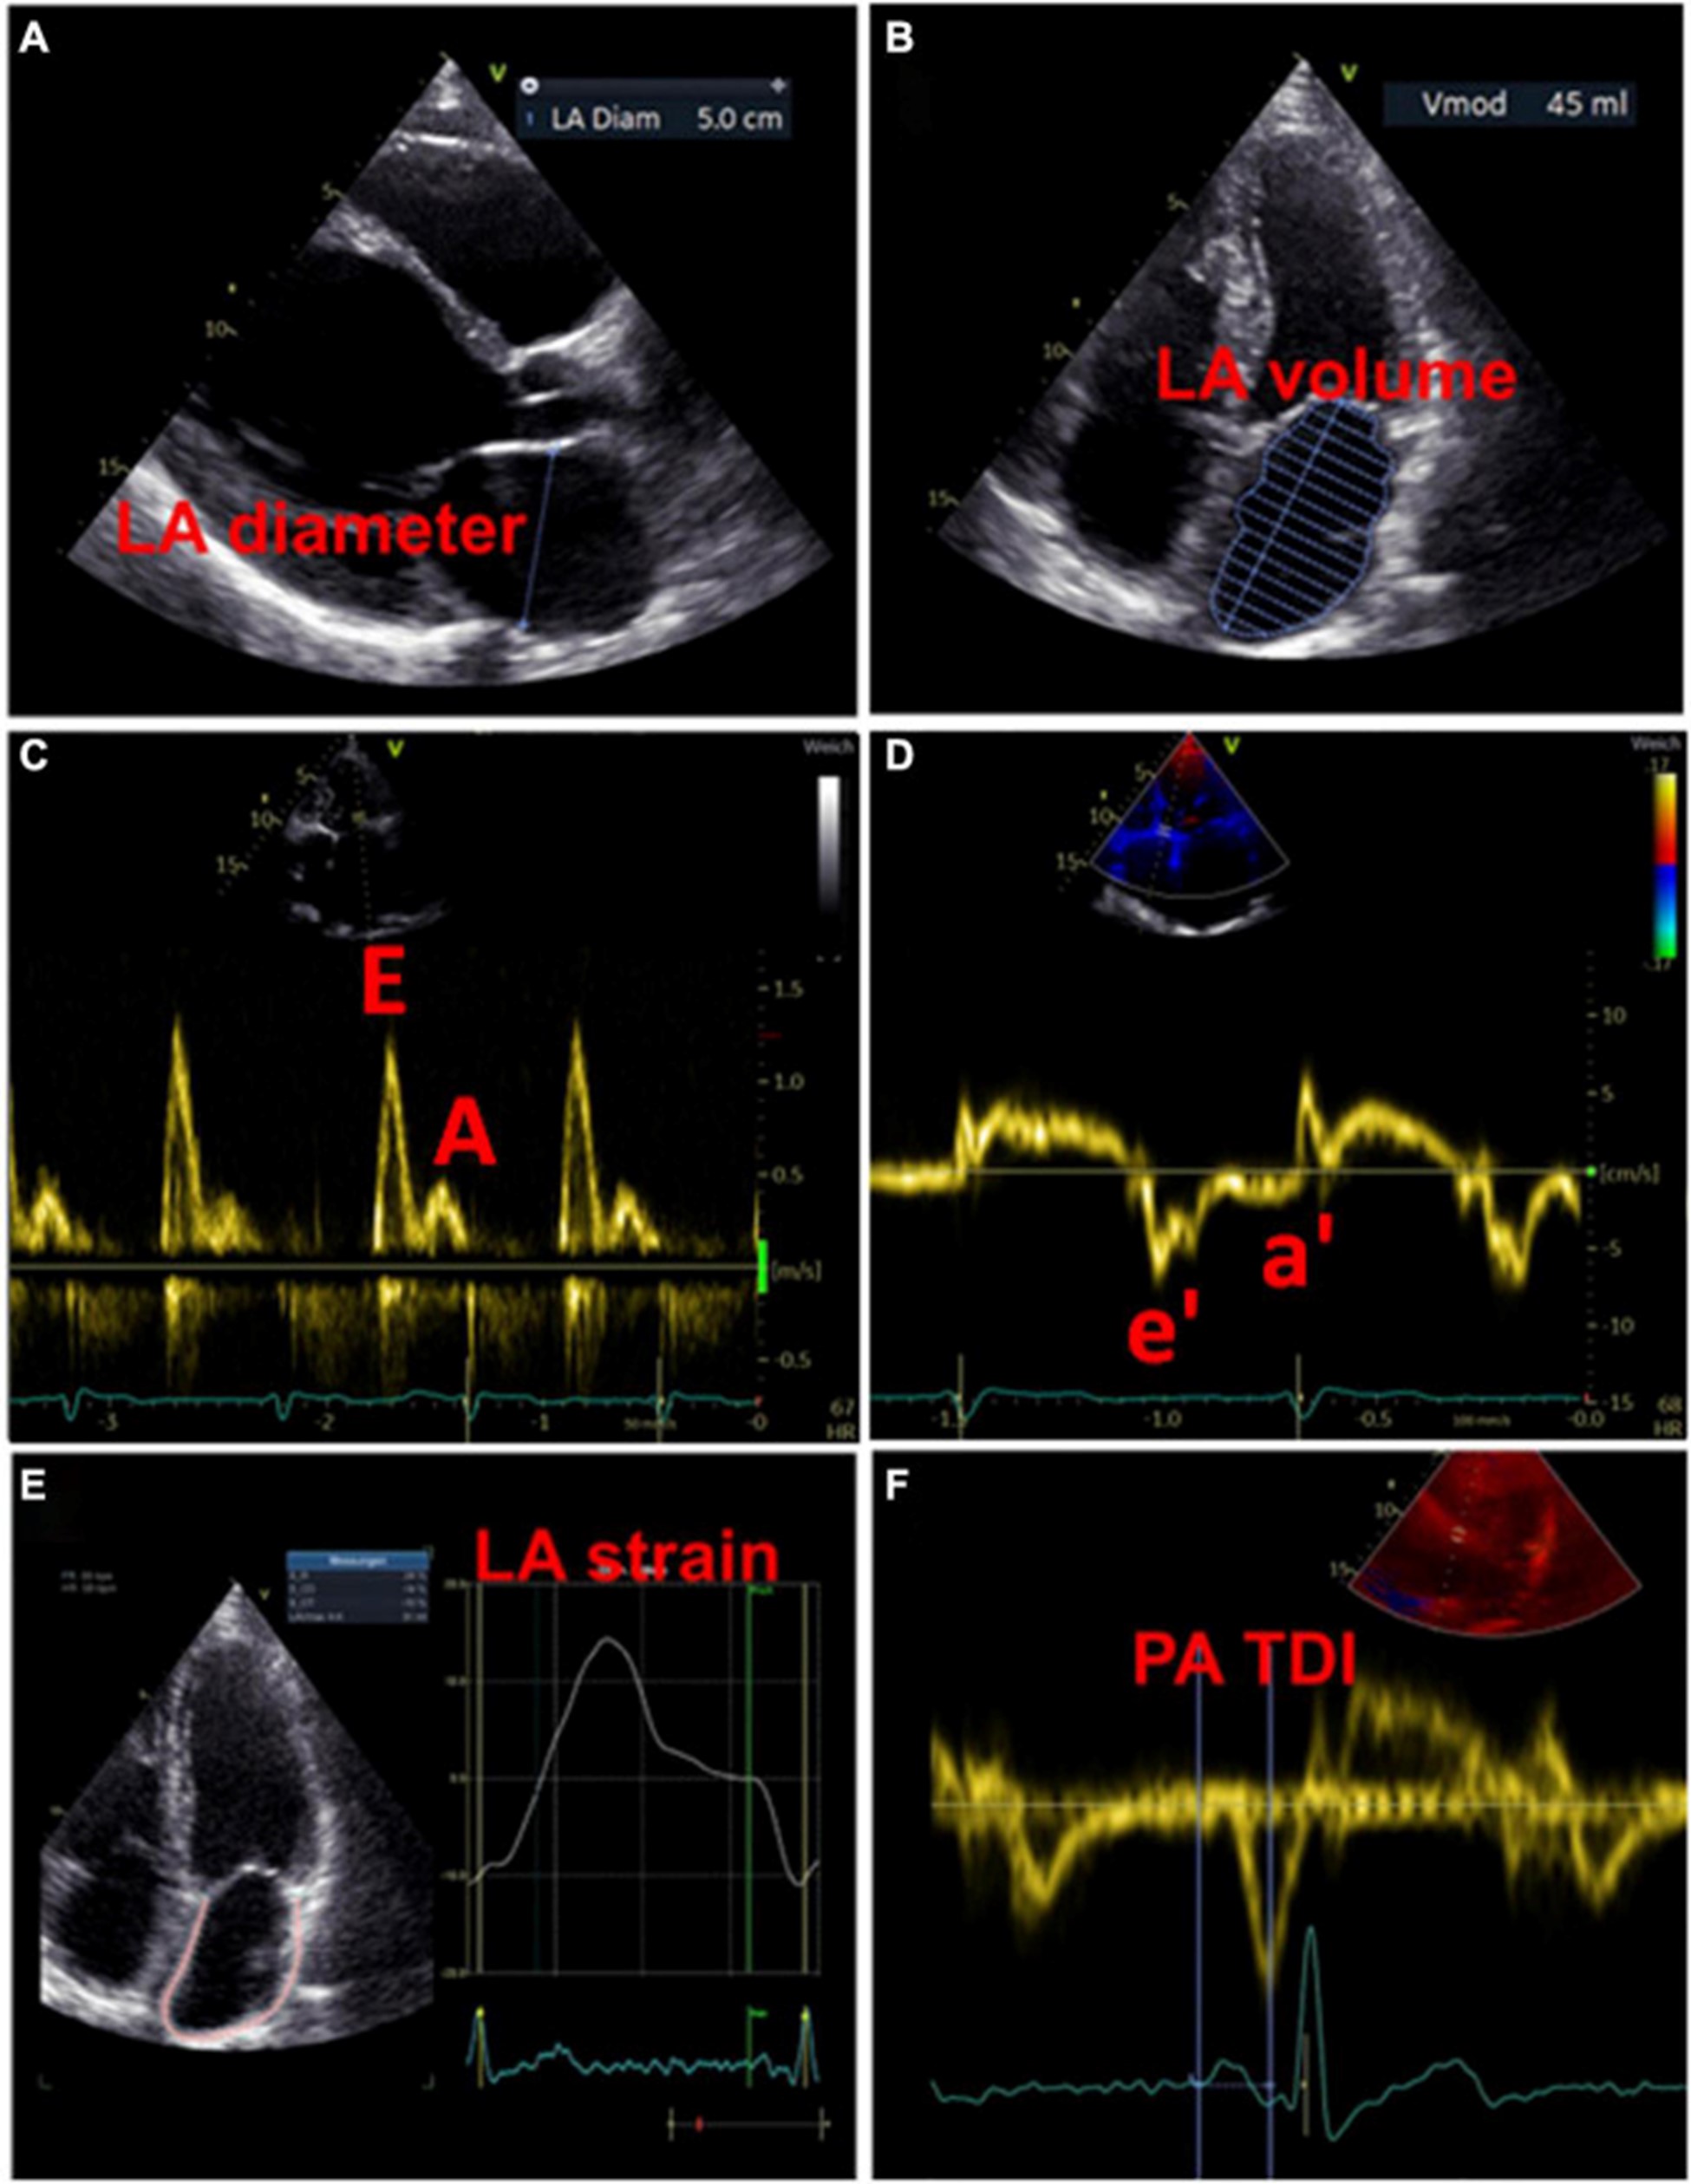

左心房大小

用于估计 LA 大小的一个广泛使用的参数是 LA 直径 (图 3A)。在 AFFIRM 研究中,增加的 LA 直径与复发性 AF 相关,但与卒中风险无关 。然而,一项荟萃分析揭示了较大的 LA 直径与中风和血栓栓塞事件的发生率之间存在关联 。此外,大 LA 直径和 LA 体积指数都被证明是主要不良心血管和血栓栓塞事件的预测参数,特别是在没有 AF 的年轻患者中 。LA 容积指数更精确,因此更适合估计心房大小(图 3B)。增加的 LA 体积指数已被描述为心肌功能障碍的潜在早期标志物,并且经常出现在 AF 患者中,在更高的 AF 负担中频率增加 。此外,与似乎没有预测作用的最大 LA 体积相比,最小 LA 体积与新发 AF 和主要不良心血管事件的发生率密切相关 ( 53 – 56 )。

图 3:用于检测左心房心肌病的超声心动图测量示例。(A)测量左心房舒张期的直径。(B)左心房舒张期左心房容积的测量。(C)左心室舒张期的经口流入曲线:第一波代表 E 波(血液被动流入左心室),第二波代表 A 波(左心房主动收缩)。(D)左心室心肌运动的组织多普勒成像,结合(C)心房功能和左心室舒张末期压力的测量结果。(五)左心房的应变分析。(F)测量从 P 波开始(作为心房电活动开始)到 a' 波峰值(心房收缩的机械反应)的 PA-TDI 间隔。

除了代表结构重构的 LA 大小异常外,心房功能评估可能为左心房心肌病的存在提供进一步的重要指标。LA 扩大和 LA 排空分数降低都是 AF 患者的常见现象,LA 大小与排空分数呈负相关 。最近,Eichenlaub 等人。评估了 AF 患者的 LA 排空分数,用于诊断左心房心肌病和预测 PVI 后心律失常复发 。LACM 定义为心内膜接触标测在 0.5 mV 阈值时LA 低电压区域 ≥ 2 cm 2 。LACM 患者的 LA 排空分数低于没有左心房心肌病的患者(27 对 41%,p < 0.0001)(43)。此外,LA 排空分数 < 34% 是 LACM(曲线下面积为 0.846)和 PVI 后心律失常复发的重要预测因素(57)。

多普勒超声心动图

此外,可以通过脉冲波多普勒测量和组织多普勒成像来评估 LA 功能。LA 功能受损可能提示 LACM,在使用多普勒超声心动图的研究中,这与 AF 和 AF 负担等临床结果等同。表格1)。

过去,已经研究了许多与二尖瓣血流和舒张期心肌运动相关的超声心动图参数与 LA 功能和临床事件的关联 。然而,尚未确定适合诊断左心房心肌病的参数和相应的临界值。

虽然 LA 传导功能(以二尖瓣 E 波速度为代表)随着 AF 负荷的增加而增加,但 LA 收缩功能(以二尖瓣 A 波速度和二尖瓣环组织多普勒 a' 速度为代表)具有相反的效果。

。早期 [E] 和晚期 [A] 舒张期充盈波的比率增加与 AF 风险之间存在关联。此外,描述了峰值 A 波速度和 AF 风险之间的 U 形关系 。

二尖瓣环“e”波速度降低和 E/e 比增加表明左室舒张功能受损。有证据表明后一个参数也适用于评估 LA 功能和压力 (图 3C、D)。

通过组织多普勒成像持续时间评估的总心房传导时间

通过组织多普勒成像持续时间评估的总心房传导时间,代表超声心动图得出的总心房传导时间,是结构和电心房重塑的吉祥标志,在窦性心律期间测量为 P 波开始之间的时间间隔在表面心电图上的导联 II 和超声心动图上左室侧壁的组织多普勒成像 (TDI) 跟踪上的 A' 波峰值 (图 3F)。PA-TDI 持续时间延长与节律控制干预后新发 AF、术后 AF 和 AF 复发相关 。在 AF 患者中,血栓栓塞风险的评估通过增加 PA-TDI 持续时间值得到改善。迄今为止,尚未建立 PA-TDI 持续时间的标准参考值。然而,如果每个超声心动图实验室通过常规获取 PA-TDI 值来确定自己的正常值,则可能会改善对 AF 相关结果的风险评估 。

在过去几年中,3 维和 4 维超声心动图改善了 LA 体积测量的选择。使用 3 维和 4 维超声心动图的研究通过异常 LA 壁延迟增强来定义 LACM(表格1)。最近,在通过 4 维超声心动图调查 LA 纤维化的 LOOP 试验的子分析中,观察到最小 LA 体积、LA 排空分数和 LA 储层应变与通过心脏磁共振成像 (MRI) 测量的 LA 晚期钆增强相关。56 )。LA 排空分数对预测高 LA 晚期钆增强作用最强,因此预测 LA 纤维化 。

斑点追踪超声心动图

近年来,斑点追踪超声心动图已成为通过评估组织运动来检测早期心肌变形的流行方法 。LA 应变和应变率成像提供了对心房功能重塑的见解。图 3E)。评估斑点追踪超声心动图效用的研究主要通过临床定义(例如,AF、AF 负担、AF 复发、血栓栓塞事件)或通过与电解剖标测中的异常发现进行比较来定义 LACM。表格1)。